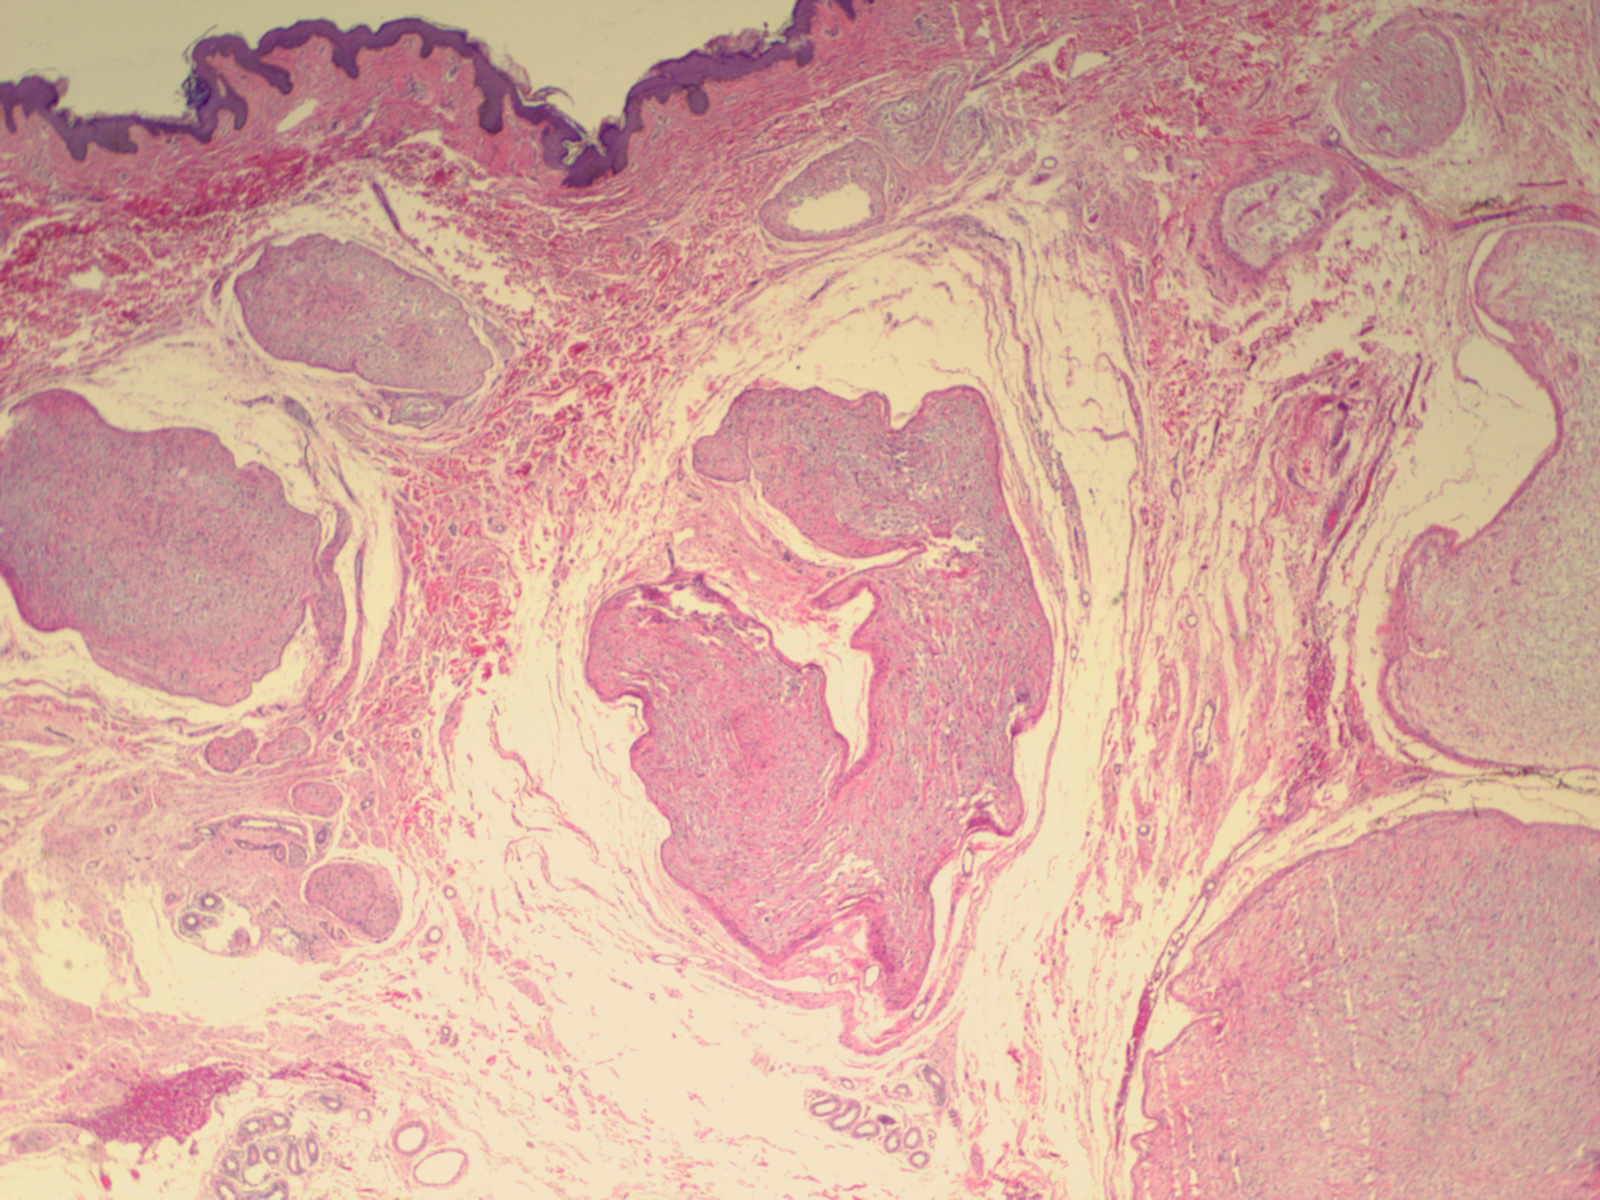

Plexiform neurofibroma = الليفوم العصبي الظفيري الشكل